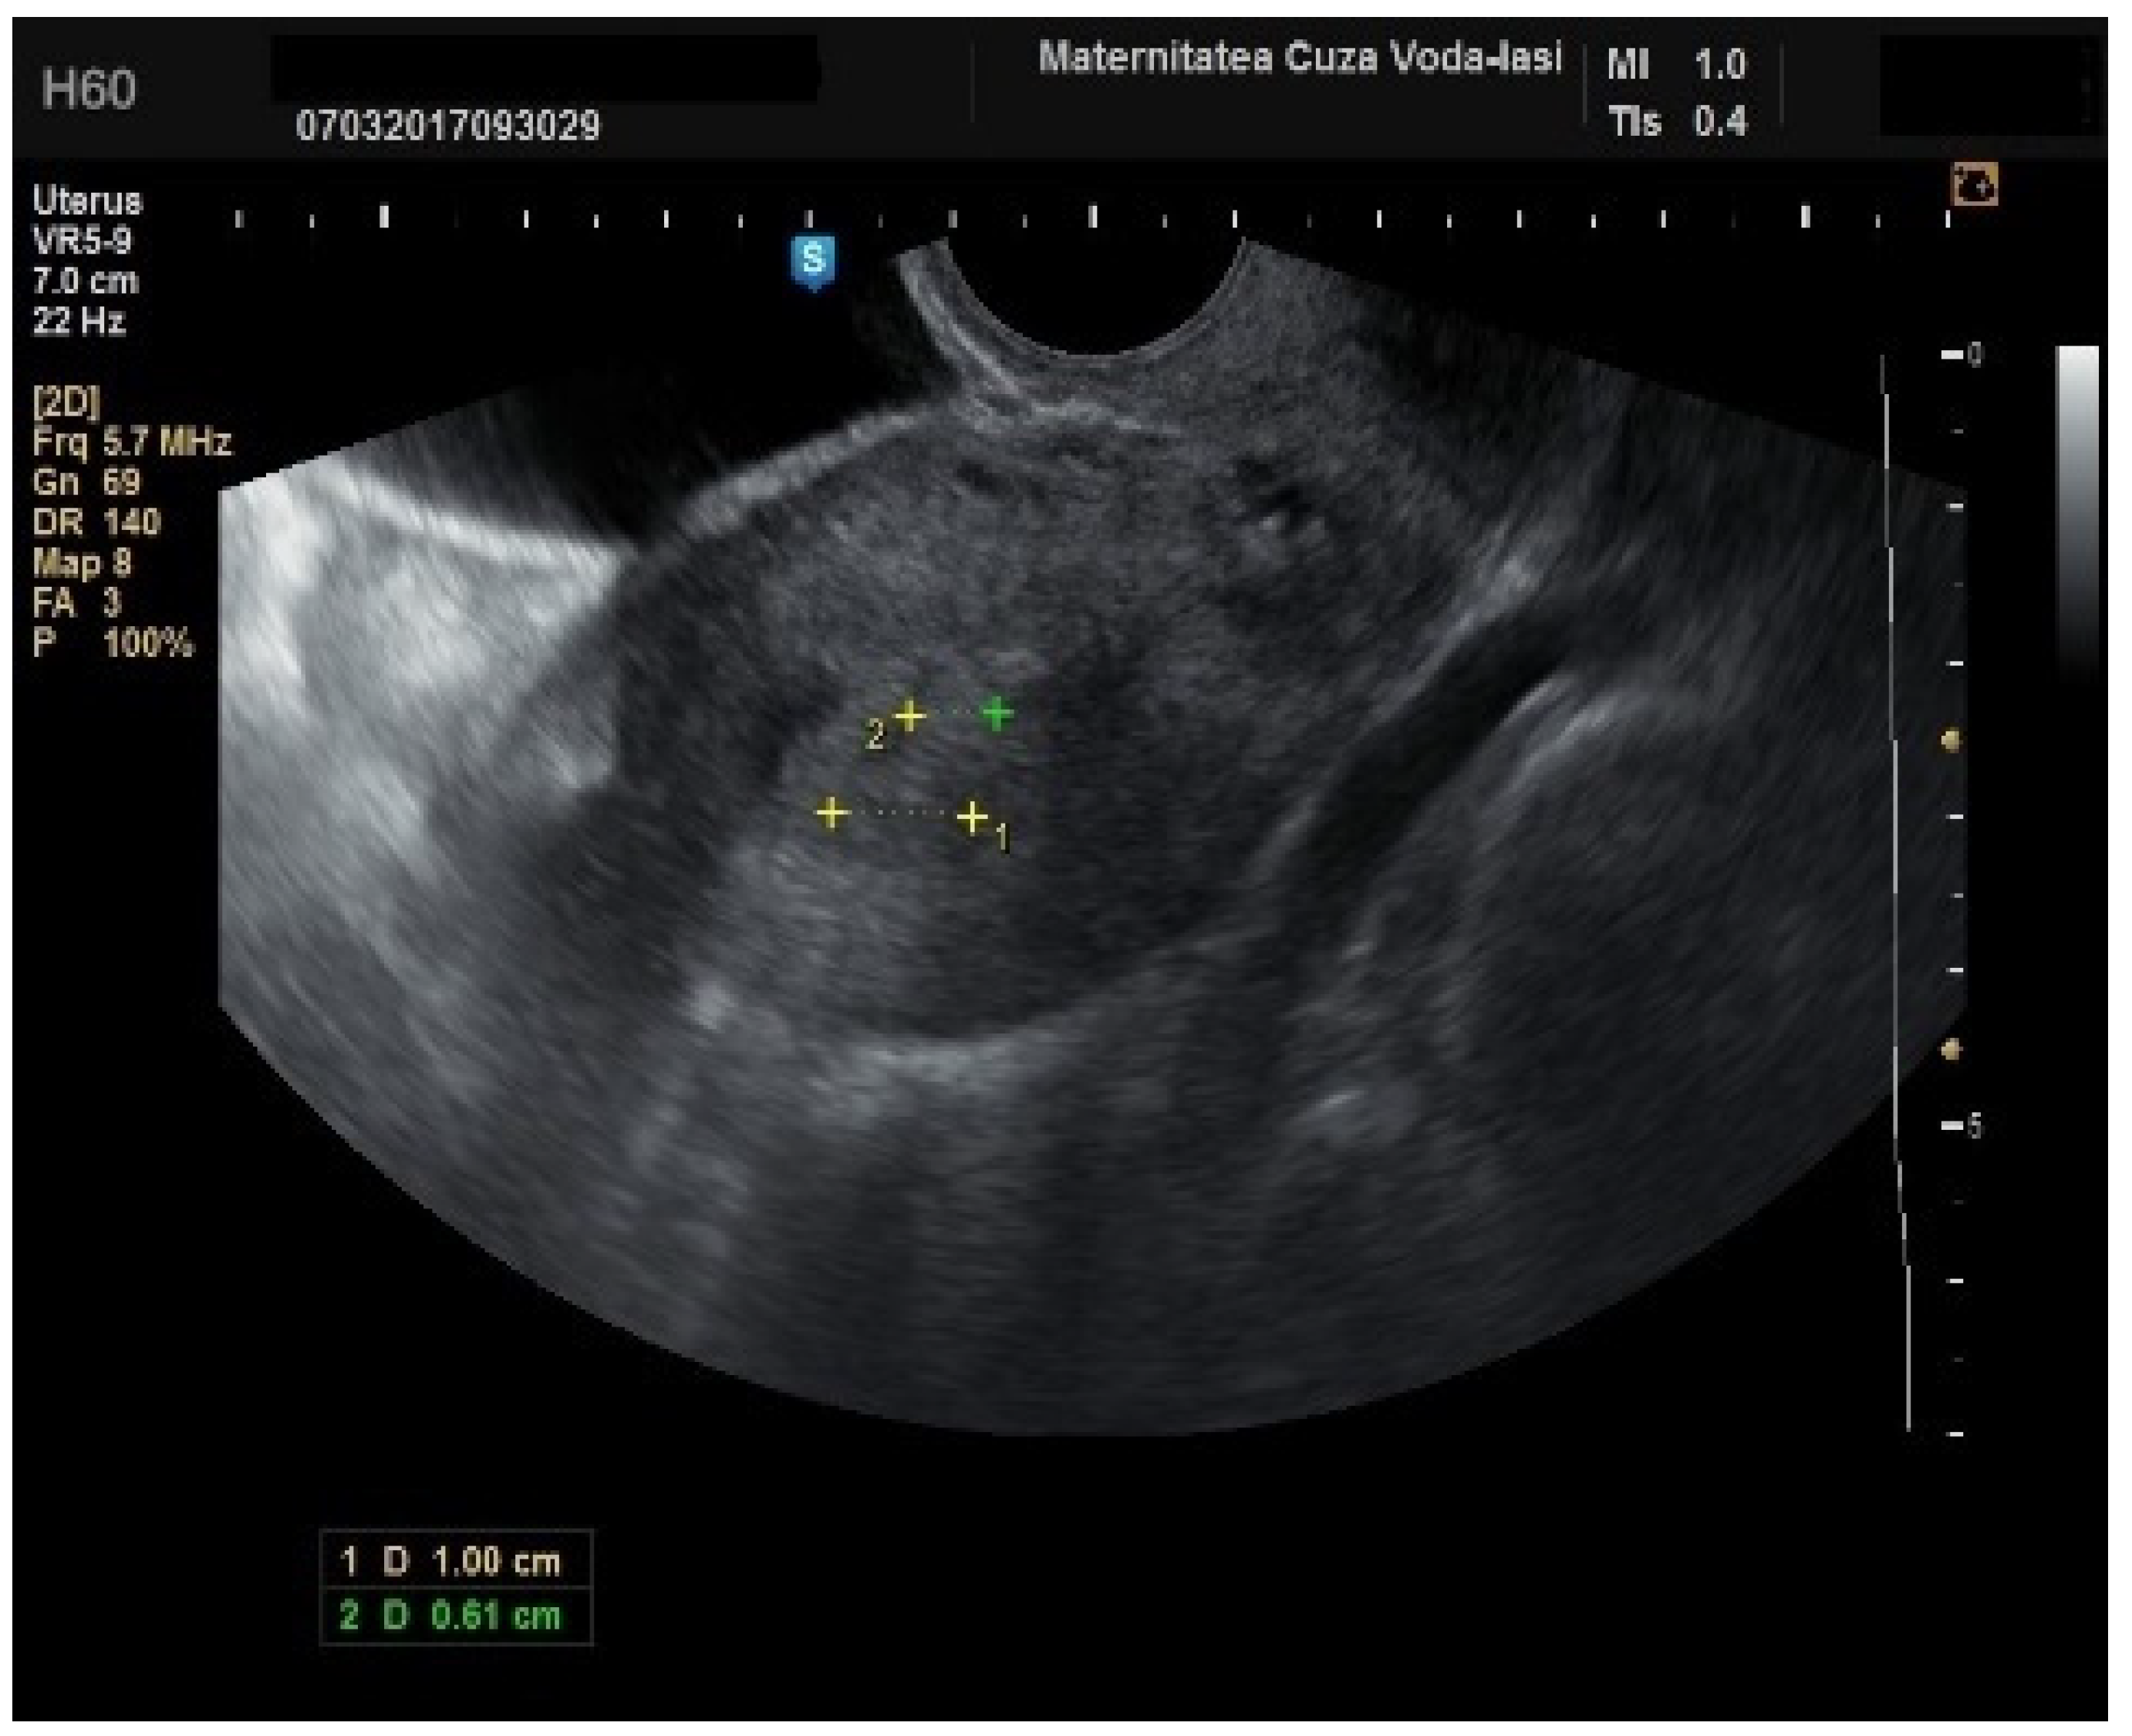

The mean age for patients with endometrial polyps was 50.70 ± 8.40 years (p = 0.001). The average endometrial thickness for the endometrial polyps was 13.68 ± 4.37 mm (p = 0.001), with a threshold value of 9.8 mm, yielding a sensitivity of 0.767, and specificity of 0.23, which lacked predictive value. There was no correlation between the internal structure of the endometrium and its echogenic homogeneity—heterogenous endometrium showed a sensitivity of 90.9% (95% CI: 0.7219 to 0.9747) and specificity of 46.51% (95% CI: 0.3251 to 0.6108) (Figure 15). The endometrial–myometrial junction remained regular in all cases of endometrial polyps. Usually, the vascular score for polyps was 1, with a single dominant vessel penetrating from the myometrium into the endometrium, either with (Figure 16) or without branching (Figure 17), although vascularization was not observed in 68.4% of participants with polyps.

Figure 17. Color Doppler imaging for assessing endometrial polyps: single vessel without branching.